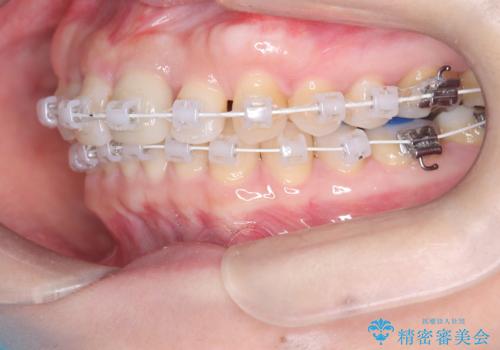

八重歯と口元のバランスを整えた矯正治療

- 「八重歯をきれいにしたい」とのご希望で来院されました。診察の結果、上顎犬歯の萌出スペースが不足しており、典型的な八重歯(叢生)の状態でした。上下の歯の中心(正中)のずれや、奥歯のかみ合わせ(臼歯関係)のアンバランスも見られたため、単に見た目を整えるだけでなく、全体的な機能改善も必要と診断しました。

スペースを確保するために抜歯を行う選択肢もありましたが、歯列の幅や骨格とのバランスから判断し、上顎の奥歯を後方に移動させることでスペースを作る方針を立てました。そのため、まずリンガルアーチ(内側に装着する固定式装置)を用いて奥歯を遠心移動させ、その後ワイヤー矯正で歯列全体を整える治療計画を立案しました。

初期段階では、リンガルアーチを上顎に装着し、奥歯を少しずつ後方へ移動させていきました。これにより前歯部の歯列に十分なスペースを確保。その後、マルチブラケット(ワイヤー矯正)を用いて、突出した八重歯を正しい位置に誘導しながら、歯並び全体を整えていきました。

治療中は咬合バランスや歯列の中心(正中)の位置にも注意を払い、最終的には上下の正中が一致し、左右の臼歯関係も理想的な形に改善されました。見た目の変化はもちろん、かみ合わせの安定や清掃のしやすさも向上。